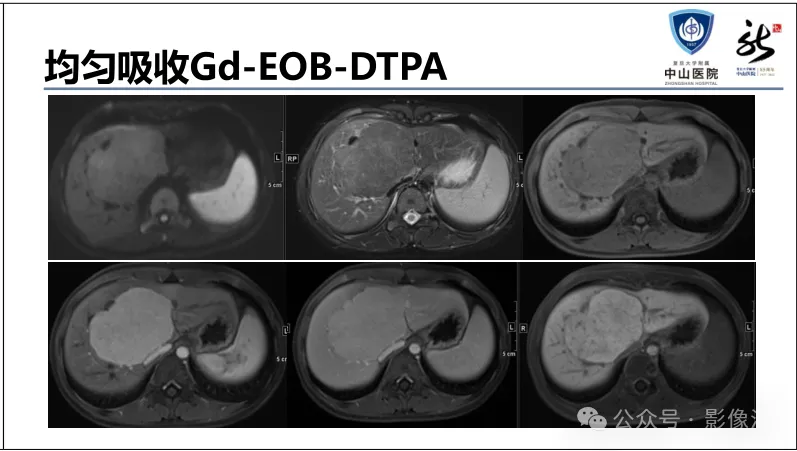

>【精品课件】如何正确判读肝胆特异性对比剂增强图像?

肝胆特异性对比剂增强肝胆图像判读方法与策略,课件来源于网络,作者复旦大学附属中山医院放射科饶圣祥教授。